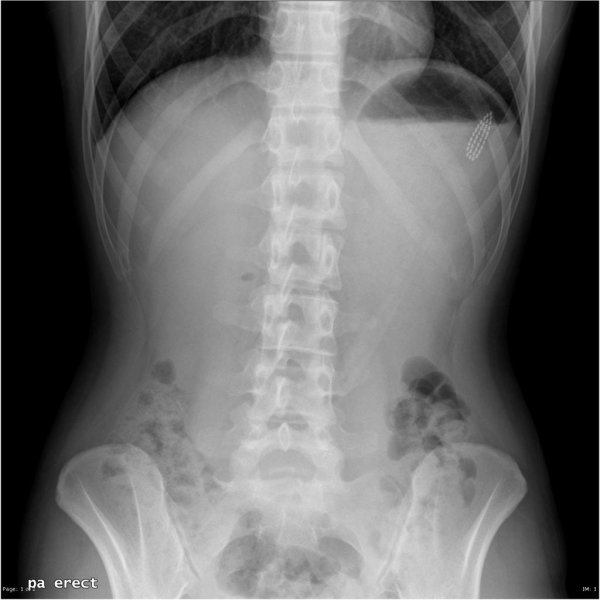

Специалисты по рентгеновской диагностике регулярно сталкиваются с посторонними предметами внутри тела человека. Обычно лишние предметы попадают в пищеварительную систему из-за неосторожности при еде или во время неудачных любовных игр. Почти всё удается вытащить — с хирургическим вмешательством или без него. выбрал самые необычные находки радиологов, которыми они делились на сайте Radiopaedia.org.